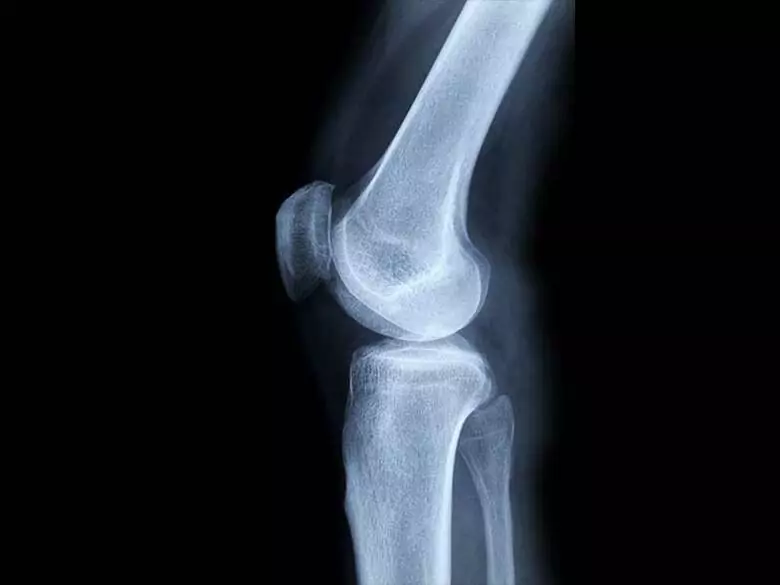

Obwohl er nicht die häufigste Krebsart ist, handelt es sich um eine sehr bösartige Erkrankung, die sich schnell entwickelt und Metastasen bildet. Primäre bösartige Knochentumore sind schwer zu diagnostizieren. Aufgrund ihrer Lage und der bekannten Ursachen können keine vorbeugenden Maßnahmen angezeigt werden.